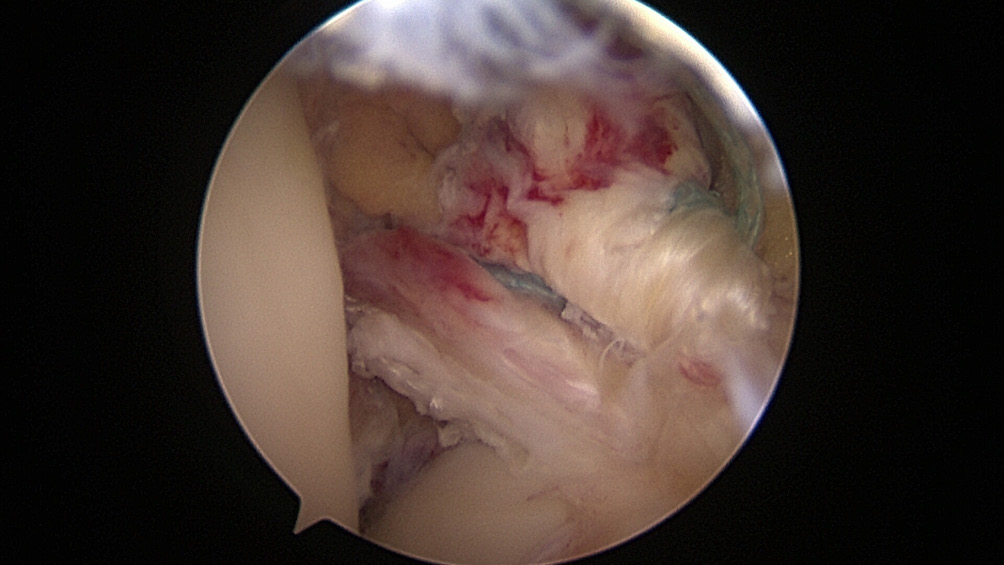

All the patients were operated on by the same team, using the same surgical technique and Neoligaments (Neoligaments) (Figure 1) or FiberTape (Biomet) (Figure 2) graft. It was fixed using Endobutton (Smith-Nephew, Watford, UK) on the femur and the interference screw, ComposiTCP30 (Biomet), on the tibia. It was prepared using the “outside-in” technique with the aimer device (Figure 3, Figure 4, Figure 5, Figure 6, Figure 7, Figure 8).